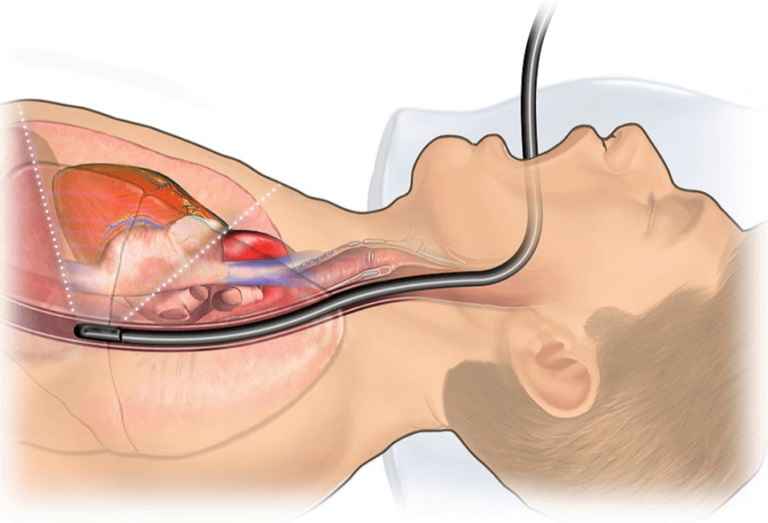

اکوی مری قلب یک نوع ویژه از اکوکاردیوگرافی است که در آن، یک پروب کوچک از طریق مری (لولهای که غذا را به معده میرساند) وارد بدن میشود. از آنجا که مری مستقیماً پشت قلب قرار دارد، پروب میتواند بدون تداخل ریهها، قفسه سینه یا چربی زیر پوست، تصاویر بسیار نزدیکی از ساختار قلب بگیرد. این وضوح بالا، امکان تشخیص لخته خون با اکوی مری و سایر جزئیات ریز را فراهم میآورد. نکته ی مهم اینجاست که شما باید این تست را در مرکز اکوی قلب تخصصی در شمال تهران انجام بدهید تا از صحت تست انجام شده مطمئن باشید.

پروب به آرامی از طریق دهان وارد مری میشود. این پروب باعث مشکل در تنفس نمیشود، زیرا از راه نای (محل عبور هوا) وارد نمیشود.